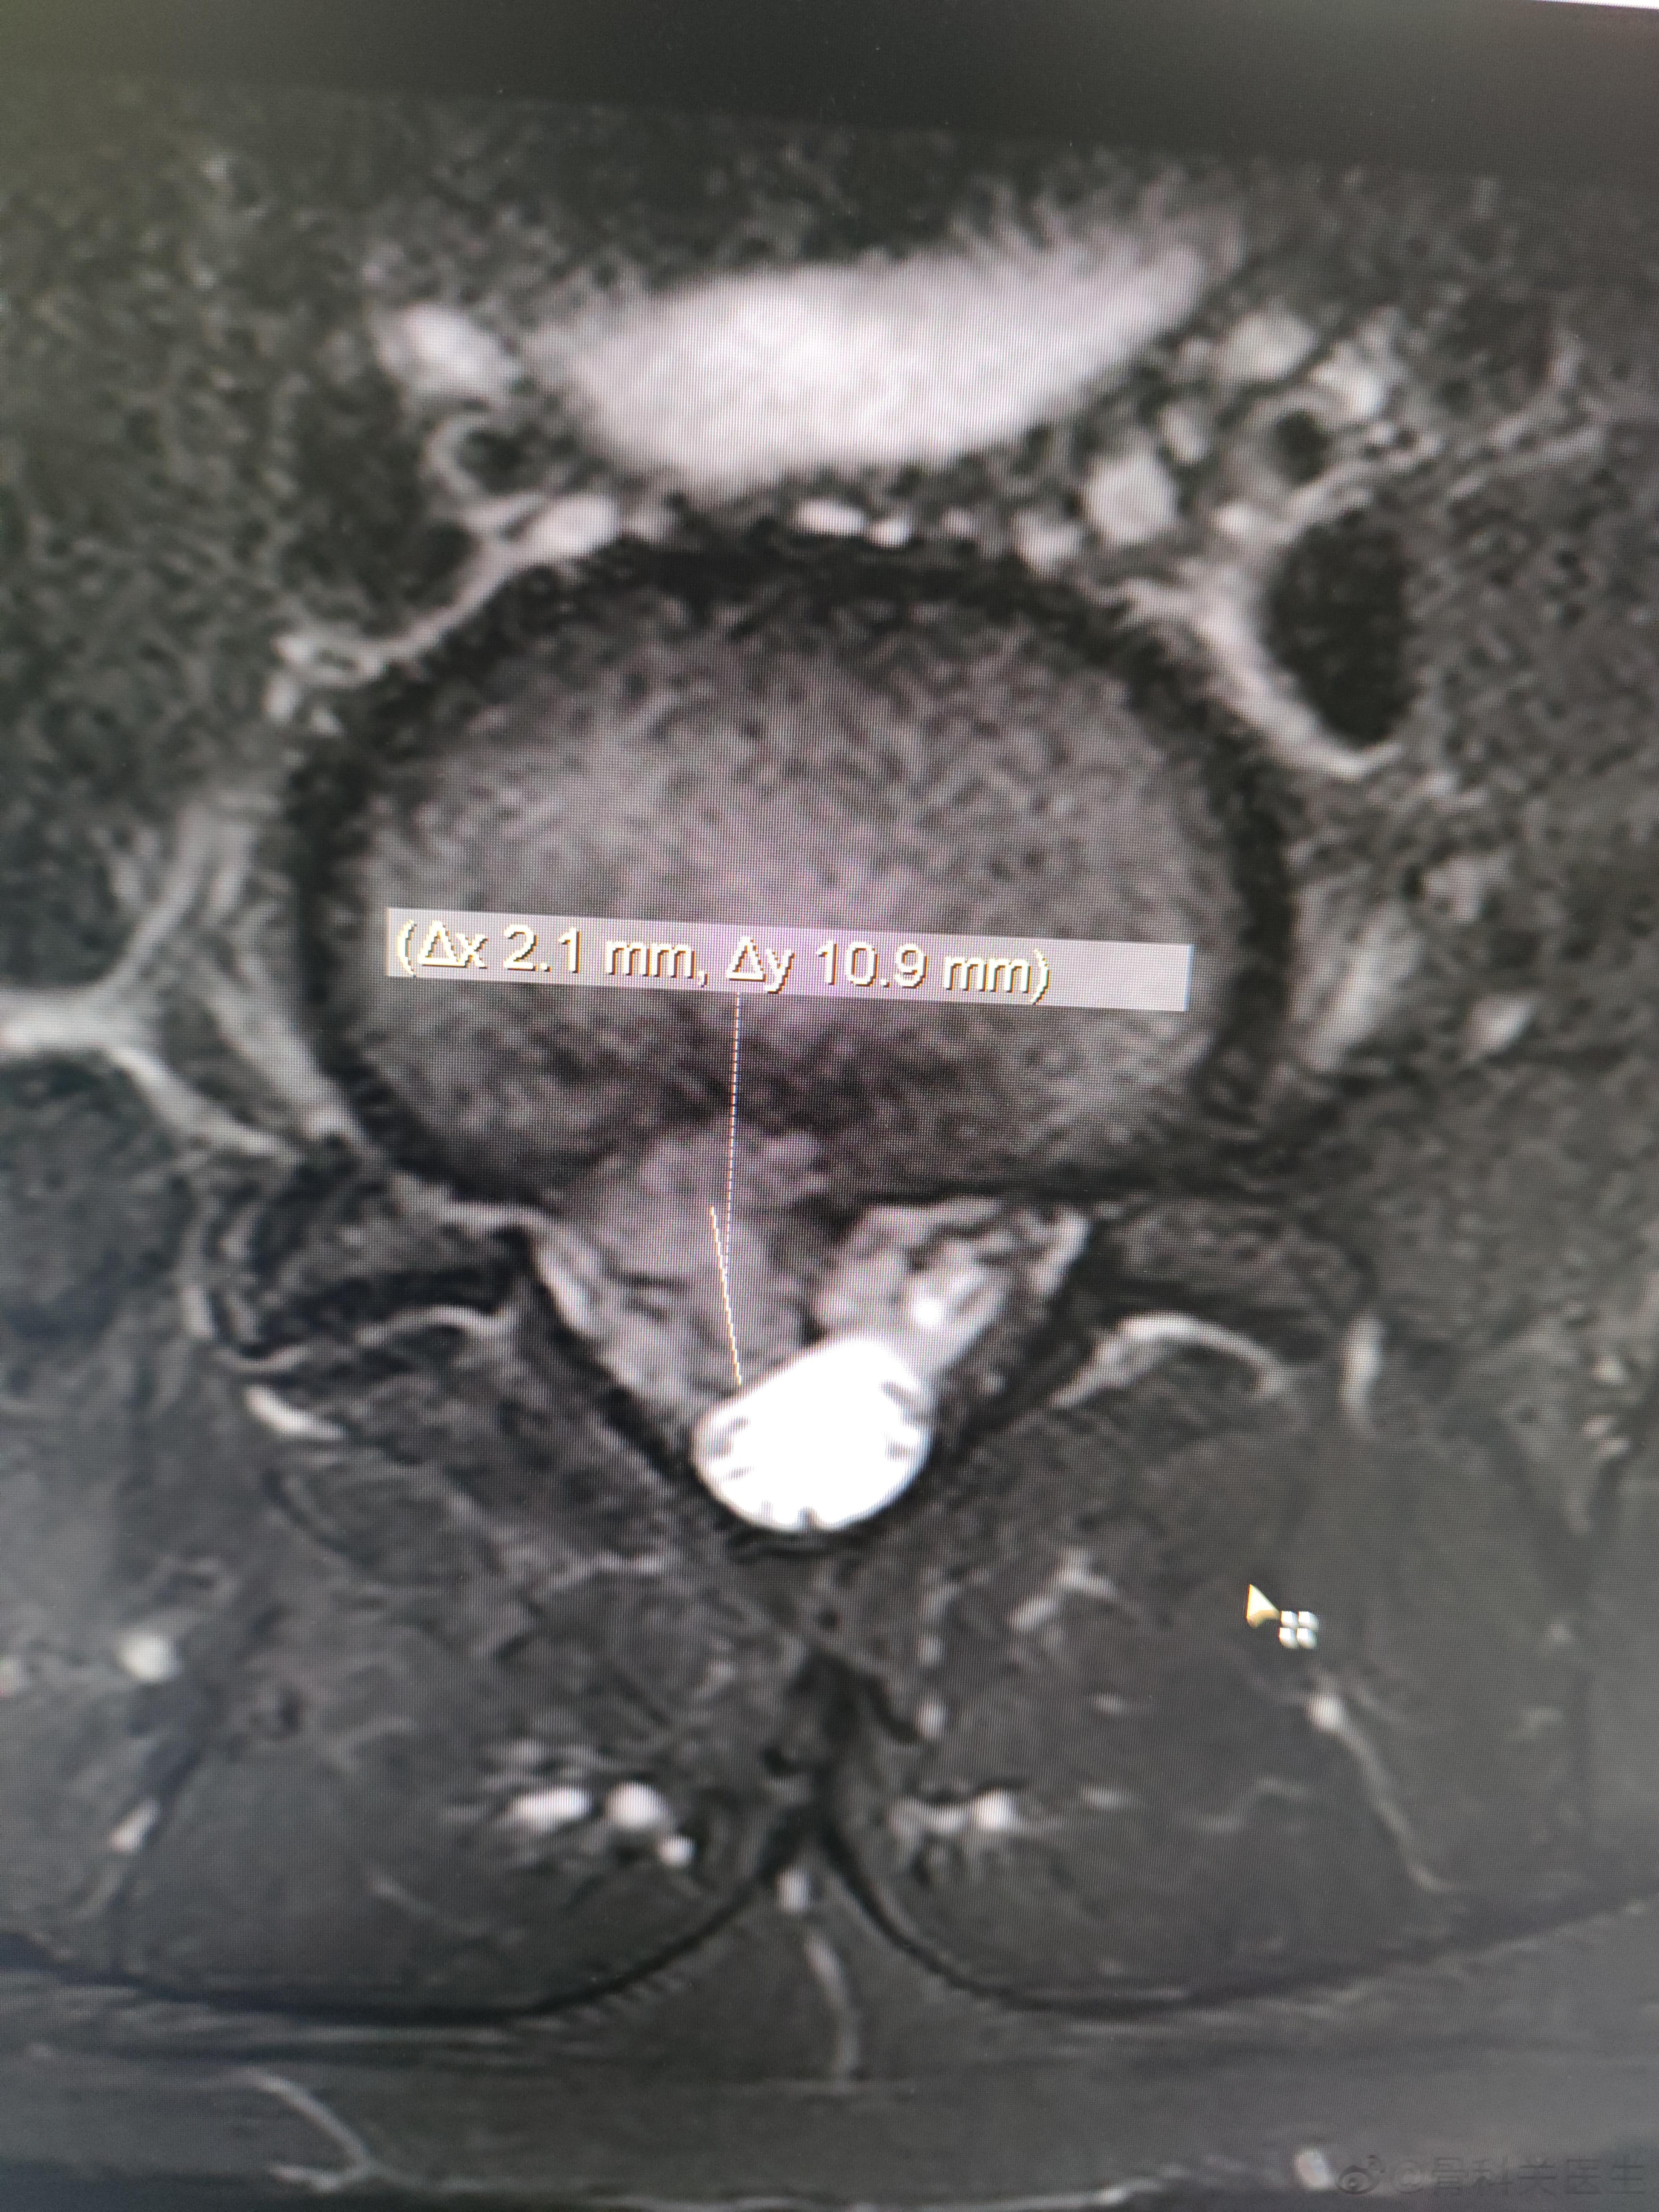

可怜的小胖孩子,一个喷嚏把自己打废了。椎间盘突出这么多,18岁大男孩,疼的哭😭

2023-04-03 20:50